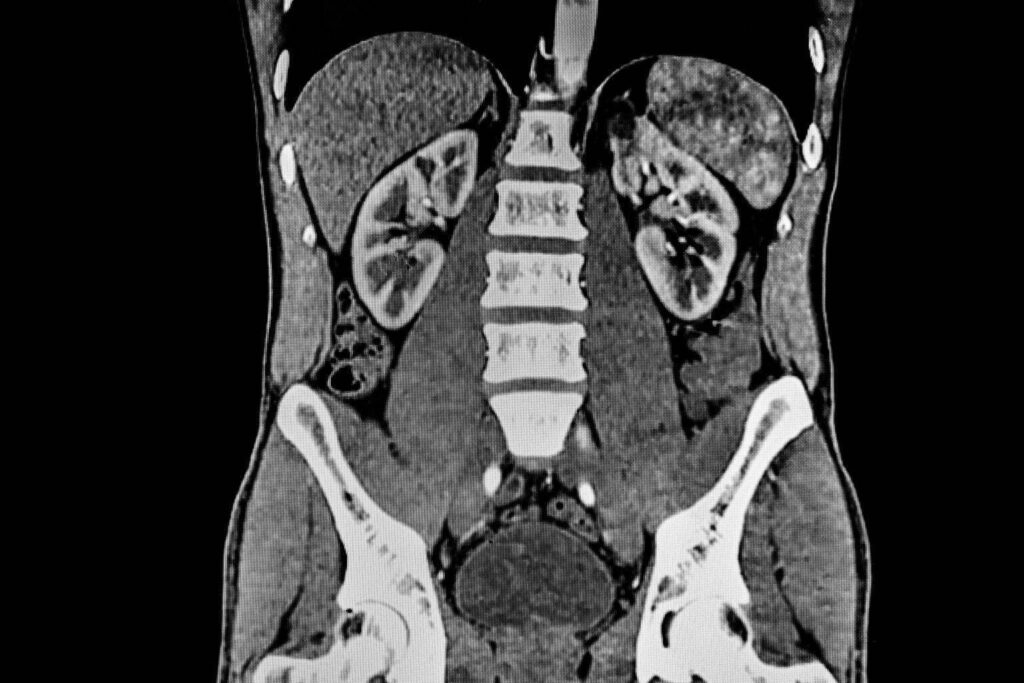

CT Abdomen Befundung – CT Abdomen welche Organe sieht man?

- Nieren – Befunde: Größe, Form und Lage der Nieren sowie Vorhandensein von Nierensteinen, Tumoren, Zysten, Infektionen oder anderen Nierenanomalien.

- Blutgefäße – Befunde: Darstellung der großen Blutgefäße wie der Aorta und ihrer Verzweigungen, Untersuchung auf Aneurysmen, Dissektionen oder andere Gefäßprobleme.

- Lymphknoten – Befunde: Erkennung vergrößerter oder abnormaler Lymphknoten, die auf Infektionen, Entzündungen oder Krebs hinweisen können.